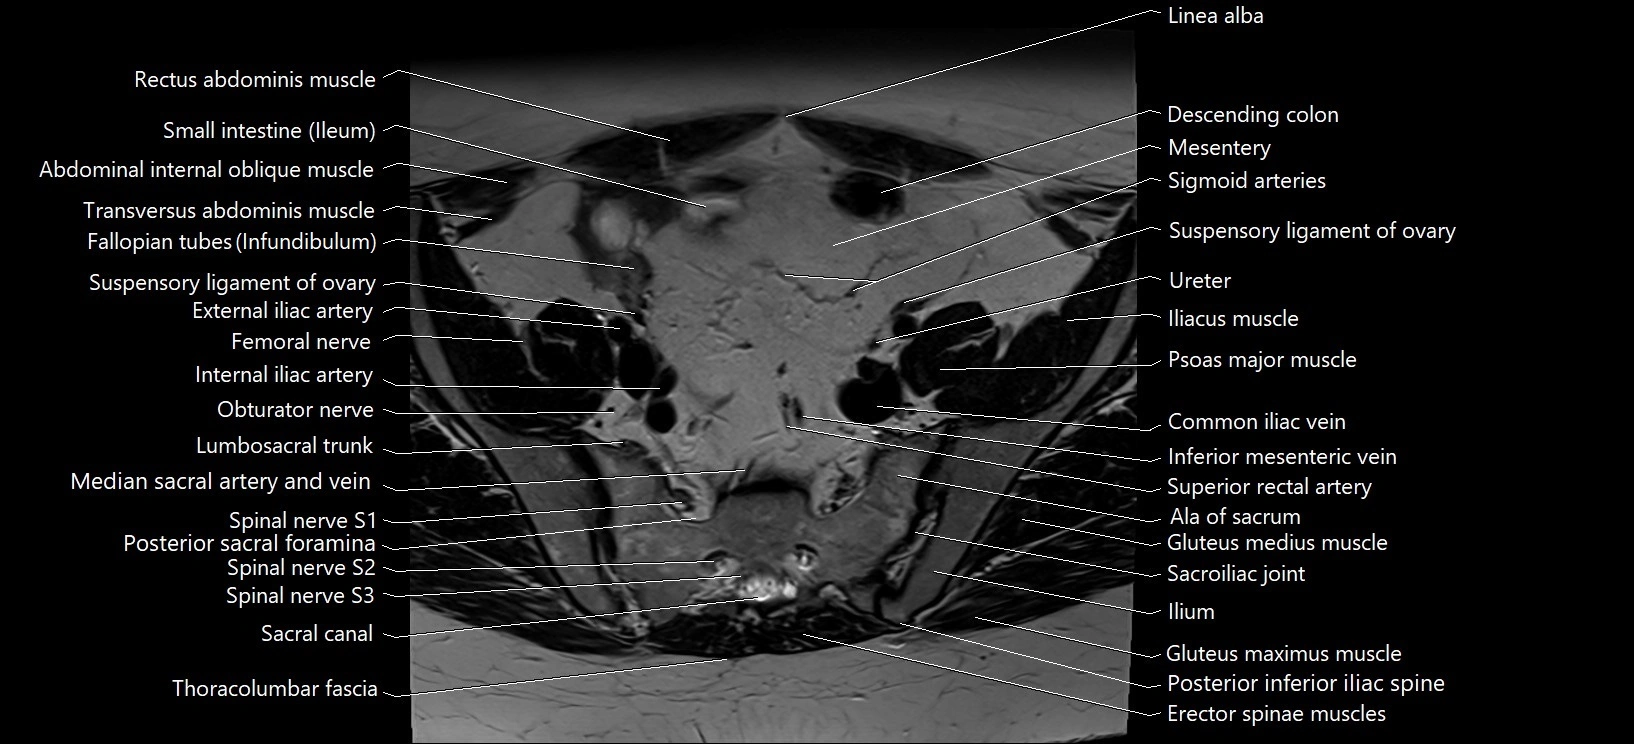

- Ala of sacrum

- Common iliac vein

- Erector spinae muscles

- External iliac artery

- Femoral nerve

- Gluteus medius muscle

- Ileum

- Inferior mesenteric vein

- Lumbosacral trunk

- Posterior sacral foramina

- Psoas major muscle

- Sacral canal

- Sacroiliac joint

- Spinal nerve L5

- Spinal nerve S1

- Spinal nerve S2

- Spinal nerve S3

- Superior rectal artery

- Suspensory ligament of ovary